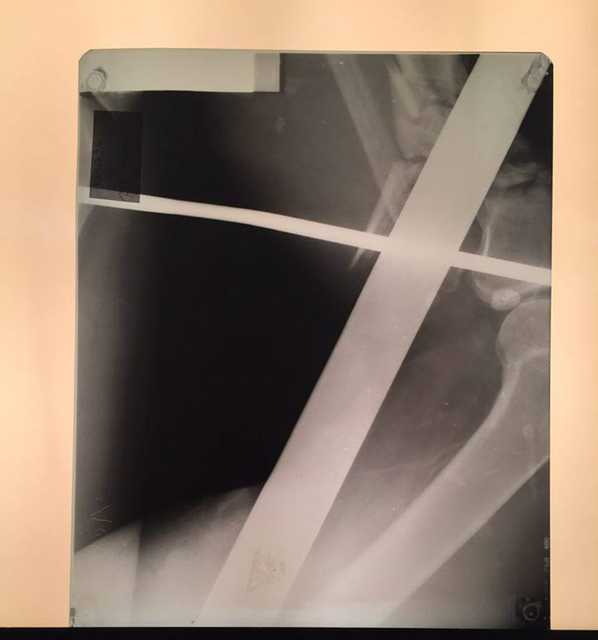

Заведующий приемно-диагностического отделения больницы имени Мечникова Петр Давыденко рассказал, что металлический профиль буквально насквозь проткнул мужчину.

«Итог: инородное тело левой голени, левого бедра, левой половины таза, левой половины поясничной области, открытый многооскольчатый перелом верхней трети левой большеберцовой кости, травматический шок», — отметил врач.

Первую медицинскую помощь пострадавшему оказали в Царичанке, после чего мужчину доставили в Мечникова. Осмотр немедленно провели дежурные травматологи, урологи, хирурги и нейрохирурги. Провели операцию по удалению инородного тела, ПХО ран, лапароцентез, а также объемное переливание препаратов крови.